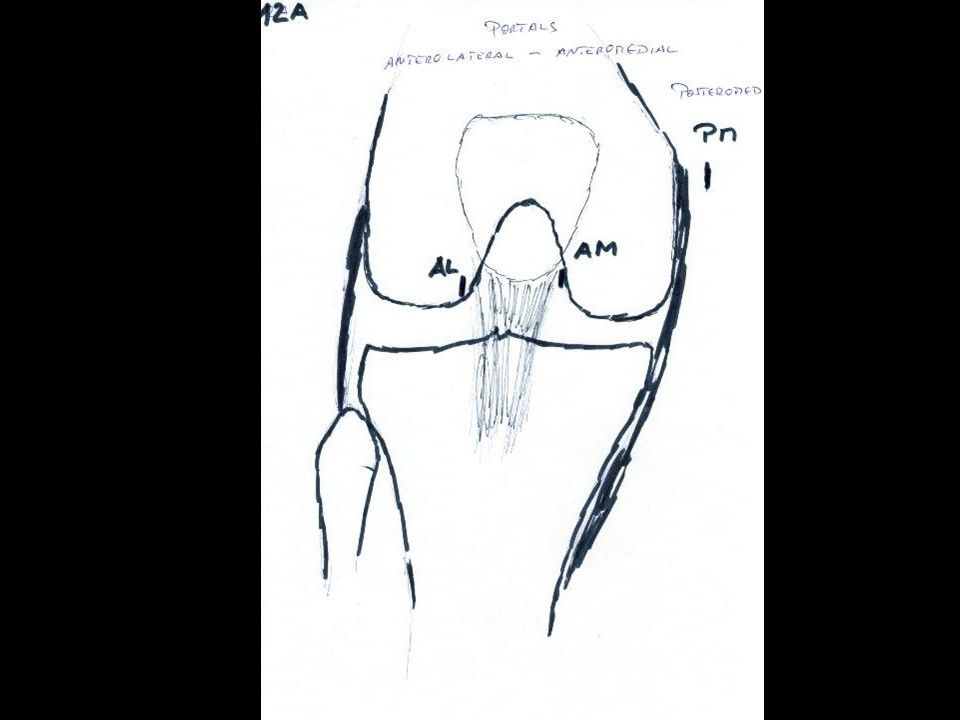

The portals for arthroscopy are primarily made anteromedial and anterolateral adjacent to the apex of the patella (Fig 15 & 16).

Fig 15 and 16 - Postion of arthroscopic approaches